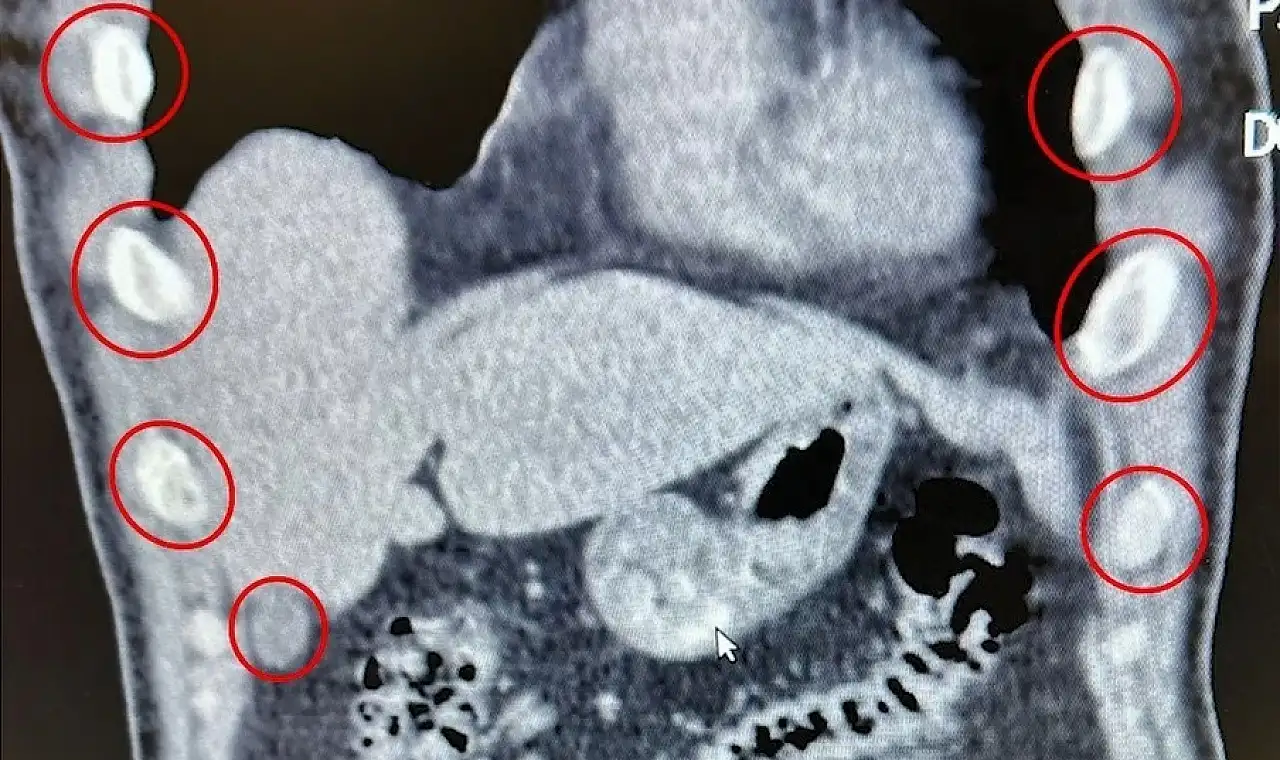

İl Emniyet Müdürlüğü Narkotik Suçlarla Mücadele Şube ekipleri, Tatvan ilçesinde durdurdukları bir otobüste yolcu olarak bulunan iki şüpheliyi gözaltına aldı. Şahısların hastanede yapılan kontrollerinde, yuttukları 136 kapsül içinde toplam 1 kilo 48 gram metamfetamin tespit edildi.